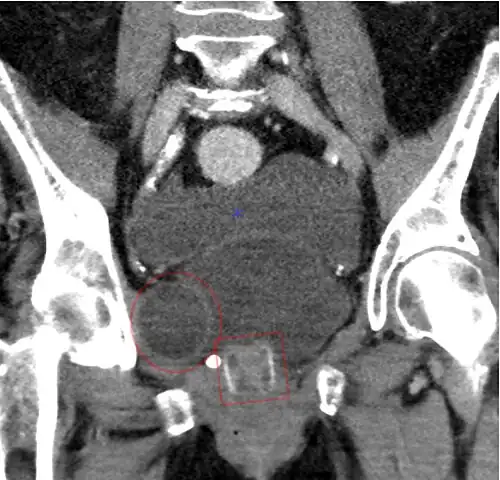

-

CT scan (coronal reconstruction) showing an AMS 800 in a woman -